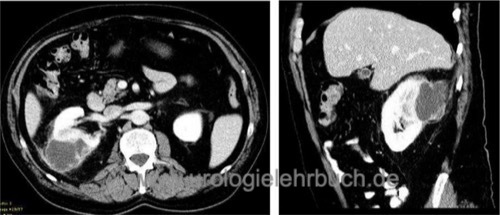

CT:

Diagnostikum der Wahl [Abb. Perinephritischer Abszess in der CT]. Der perinephritische Abszess zeigt sich als hypodenses Areal. Lufteinschlüsse sind möglich. Nach Kontrastmittelgabe zeigt sich eine Anreicherung des Randbereiches, dies entspricht der Abszesskapsel und imponiert als Ringzeichen.